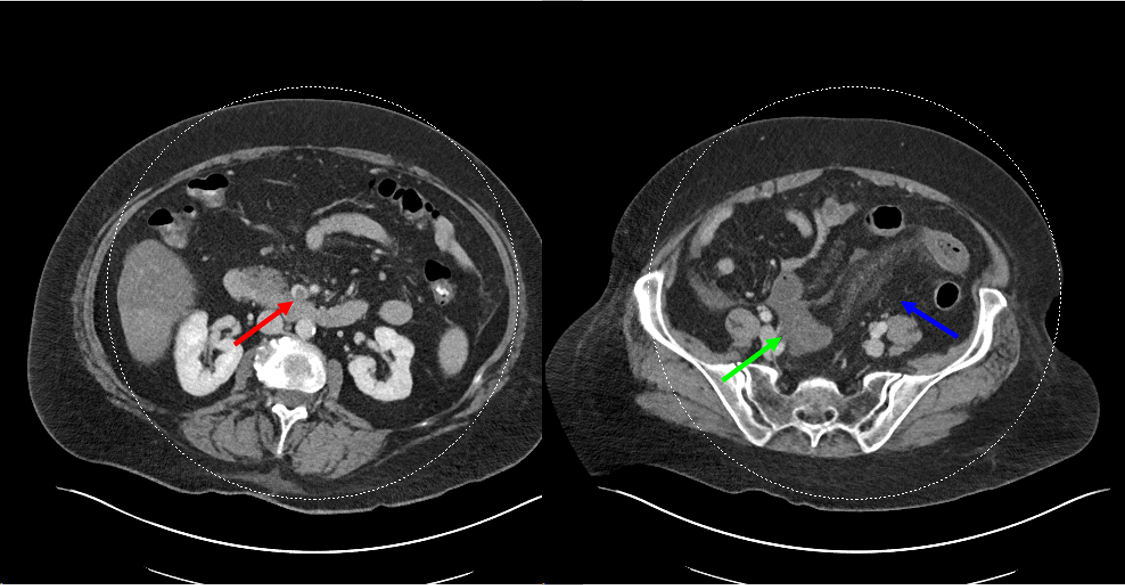

CT images show a thrombus in the SMV (red arrow). Bowel loops are thickened and hypoenhancing (green arrow). There is also mesenteric edema (blue arrow)